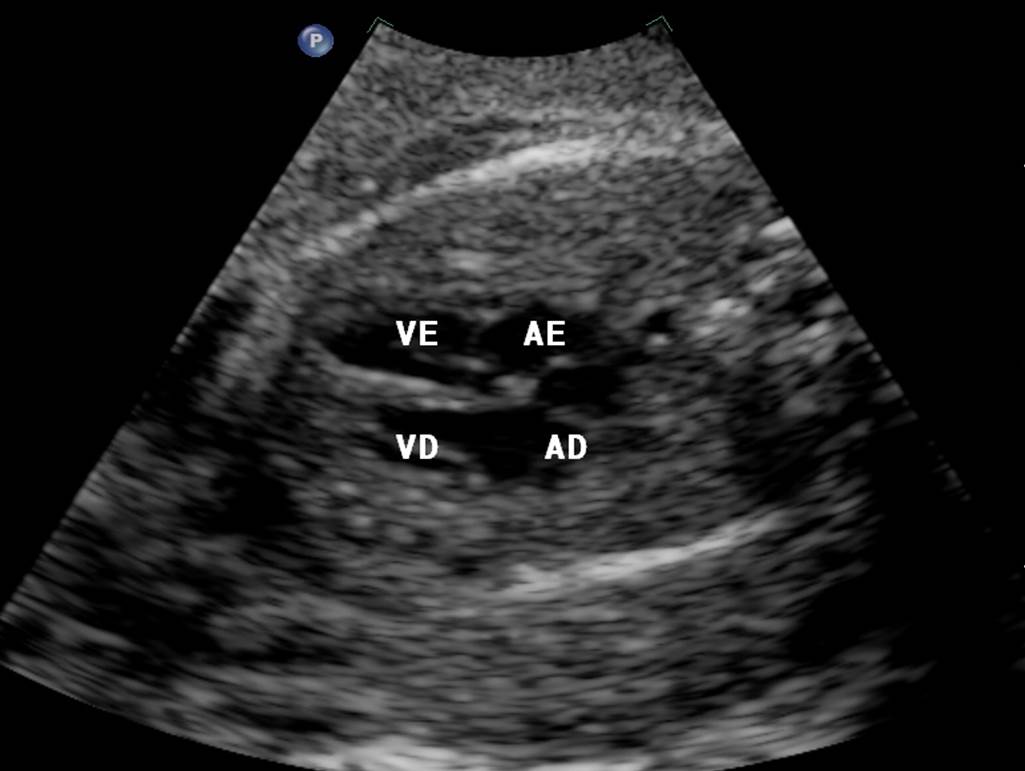

Ecocardiograma Fetal

Imagem ECO FETAL

O que é

O Ecocardiograma Fetal é um exame de ultrassom para avaliar o desenvolvimento e o funcionamento do coração do feto ainda no útero materno. Ele complementa a avaliação do ultrassom morfológico.

Indicação

Exame complementar ao ultrassom morfológico, que pode ser realizado a partir de 18 semanas de gestação, sendo a época ideal entre 24 – 28 semanas.

Pesquisa de doença congênita, que pode necessitar de intervenção cirúrgica após o parto.

Pesquisa de arritmia cardíaca fetal, que pode ser tratada ainda na fase pré-natal.

Presença de cardiopatia congênita na família.

Presença de doenças infecto-contagiosas que podem comprometer a formação do coração, como toxoplasmose, rubéola e citomegalovirose.

Uso materno de medicações que podem causar doença cardíaca fetal.

Presença de diabetes materno.

Idade materna superior a 35 anos.

Como é realizado o exame?

O médico avalia o coração fetal através de ultrassom pelo abdome materno.